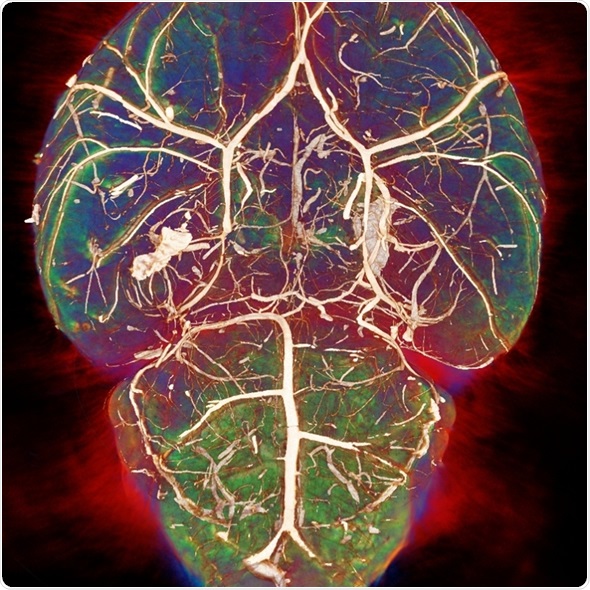

CABI is a preclinical imaging laboratory where we have about ten modalities. We started off with MRI and we have a 9.4T high-field system.

We have expanded our modalities since then and now have PET and SPECT/CT nuclear imaging, bioluminescent confocal microscopes, the OPT - optical projection tomography, and the ICON-1T system.

Image credit: Photoacoustic imaging group, UCL